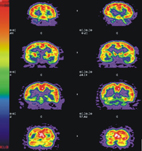

⊙ 案例:阿茲海默症患者在正子造影檢查上的表現

輕度患者

重度患者

▲圖示中紅色區域表示代謝率旺盛,藍色區域表示代謝率低下。我們可以看見臨床上症狀較為嚴重的患者,在正子檢查中明顯表現異常。